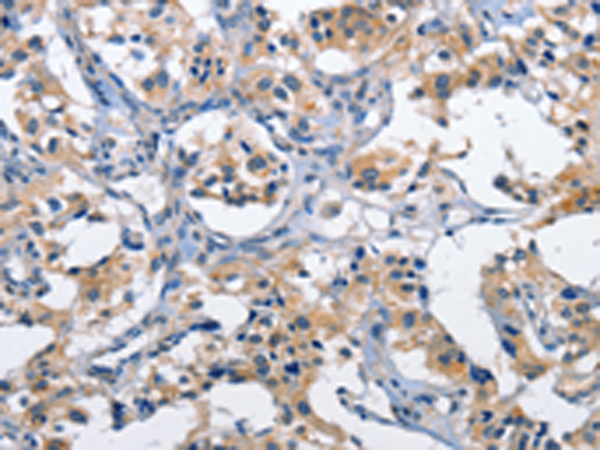

分类: 科研抗体货号: P07182别名: LIS7; PSSALRE应用: WB,IHC反应种属: Human, Mouse, Rat